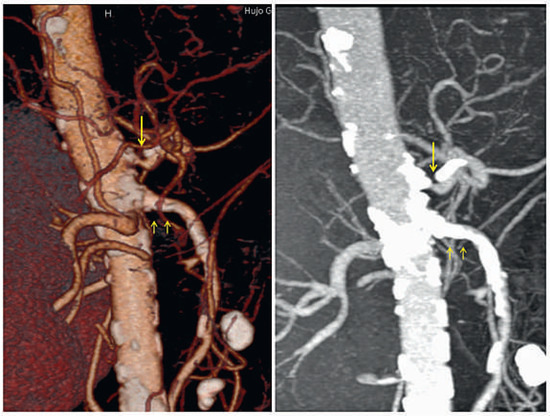

The diagnostic workup icluded gastroscopy and colonoscopy, demonstrating lesions compatible with chronic non-transmural gastric and intestinal ischaemia which were confirmed at biopsy. Computed tomographic angiography (Figure 1) showed estimated 75– 90% stenosis at the origin of the coeliac trunk and estimated 75% stenosis at the origin of the superior mesenteric artery, while the inferior mesenteric artery appeared to be free of significant stenosis. Surgical consultants deemed the patient not a candidate for surgery.

Figure 1.

Computed tomography angiography reconstructions showing severe calcified stenosis at the origin of the coeliac trunk (single arrow) and massive calcifications at the origin of the superior mesenteric artery (double arrow).